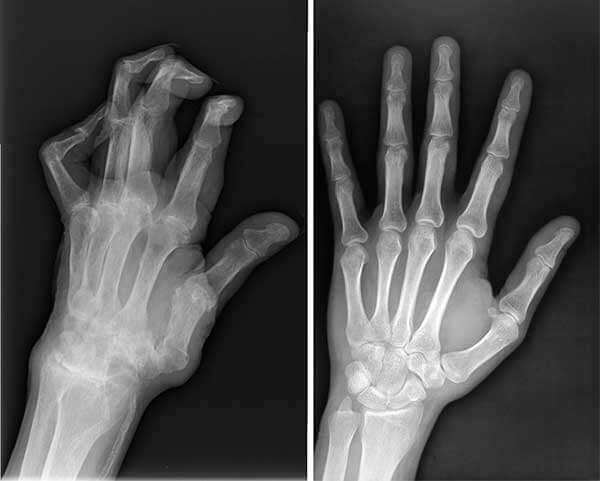

Placa de la rodilla

La radiografía mostró daños serios en mi rodilla.

Manos antes y después

Radiografías de las manos de mi esposo antes y después de Sinoflex.